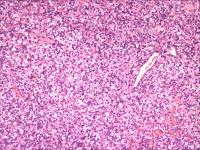

左颊黏膜肿物

性别

女

年龄

63岁

发现左颊黏膜肿物半个月,无明显疼痛

肿物1.5*1.5*1cm,界清,切面实性,红褐色,质软